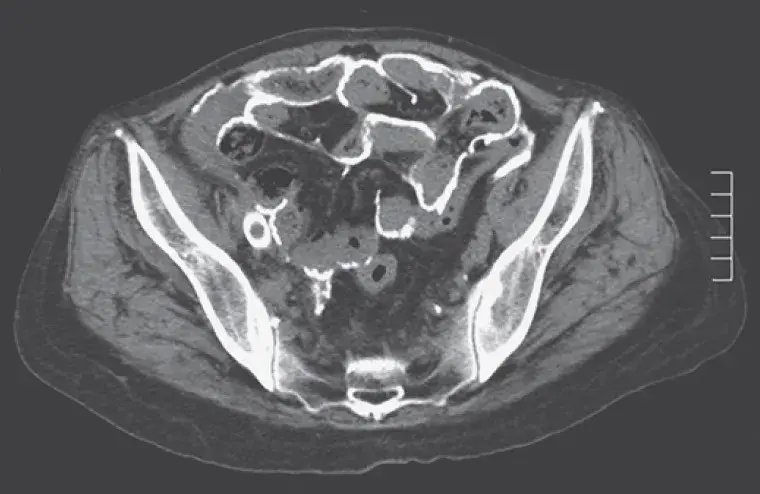

Uma causa incomum de hematúria glomerular intermitente!

Hematúria pós infecção, caso clínicos para auxiliar no entendimento de causas glomerulares comuns e raras...